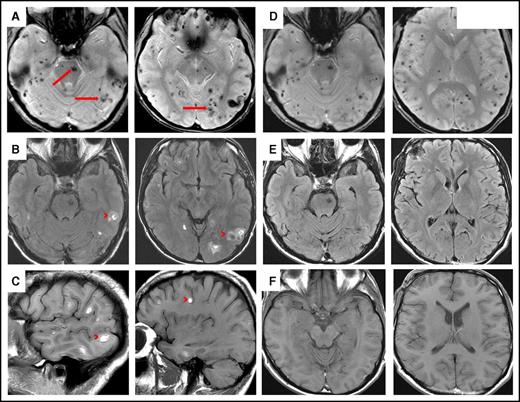

HCL involving blood, bone marrow, and brain. (A) Hairy cells in the peripheral blood showing oval to slightly irregular nuclei, ground-glass chromatin, and abundant pale blue cytoplasm with hairy projections (Wright-Giemsa stain, oil immersion lens, original magnification ×1000). (B) Bone marrow shows extensive interstitial infiltration by HCL (hematoxylin and eosin [H&E] stain, original magnification ×200). (C) Brain biopsy showing fragments of brain parenchyma (right) and area of atypical lymphoid cells (HCL infiltrate) with focal area of necrosis (left) (H&E stain, original magnification ×50). (D) Atypical lymphoid cells involving the brain are small, with slightly irregular nuclei and inconspicuous nucleoli; scattered hemosiderin-laden macrophages are admixed (H&E stain, original magnification ×400). The HCL infiltrate is positive for (E) CD20 and (F) BCL1 (immunohistochemical stains, original magnification ×200).

A brain biopsy revealed fragments of brain parenchyma and a partially necrotic area with atypical lymphoid cells (Figure 2C). These cells were small, with slightly irregular nuclei and inconspicuous nucleoli, admixed with hemosiderin-laden macrophages (evidence of hemorrhage; Figure 2D). Blood vessels in the brain parenchyma and in the lymphoid infiltrate appeared morphologically intact. By immunohistochemistry, lymphoid cells were positive for CD20 (Figure 2E), BCL1 (partial staining; Figure 2F), CD123, DBA.44, and BCL2 and negative for CD5, BCL6, and CD43. Moreover, molecular studies, performed on the brain tissue, detected the BRAF-V600E mutation. Findings were consistent with brain involvement by HCL. Fluorescence in situ hybridization study for t(11;14)(q13;q32) was attempted, but results were inconclusive because of suboptimal tissue quality and necrosis.